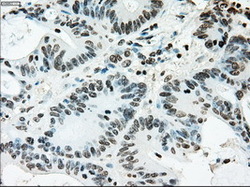

Supportive validation

- Submitted by

- LSBio (provider)

- Enhanced method

- Genetic validation

- Main image

- Experimental details

- Immunohistochemical staining of paraffin-embedded Adenocarcinoma of colon tissue using anti-ERCC1 mouse monoclonal antibody. (Dilution 1:50).